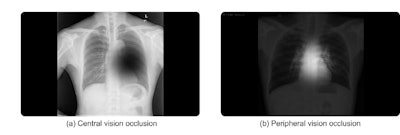

(a) Mask for central vision occlusion. (b) Mask for peripheral vision occlusion. In both conditions, the central circular area had a radius of 400 pixels, feathered with a 100-pixel gradient. The black overlay was applied with 80% opacity.(a) Mask for central vision occlusion. (b) Mask for peripheral vision occlusion. In both conditions, the central circular area had a radius of 400 pixels, feathered with a 100-pixel gradient. The black overlay was applied with 80% opacity.Scientific Reports